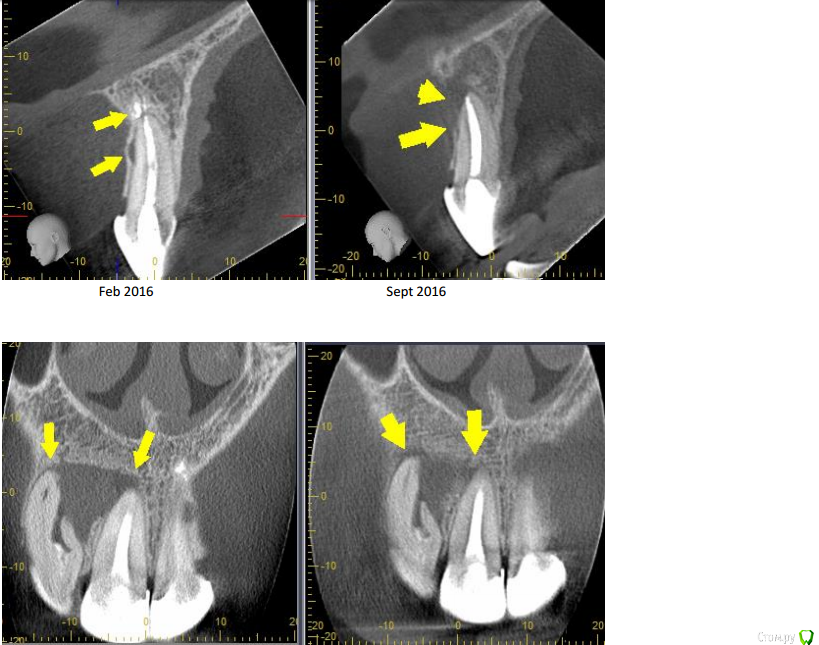

olga1985 Опубликовано 17 сентября, 2016 Автор Поделиться Опубликовано 17 сентября, 2016 добавляю снимки на сегодняшний день. врач сравнил снимки апреля и сентября. сказал, что на 21 зубе не нужно было убирать материал вышедший за корень потому что не это было причиной боли, а боковой канал. но сказал, что сейчас ничего делать не нужно, пока наблюдать. а на проблемный 21 решил, что скорее всего будет достаточно пломбирования. если нет, то будет вкрывать десну и отрезать кусок этого загнутого корня, как мне и советовал первый врач на форуме. Ссылка на комментарий

olga1985 Опубликовано 6 октября, 2016 Автор Поделиться Опубликовано 6 октября, 2016 запломбировали каналы, снимок прикрепляю 2 Ссылка на комментарий